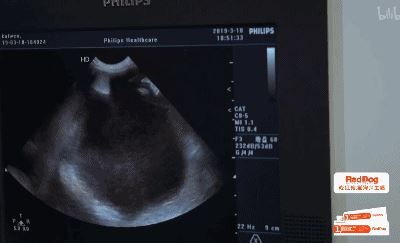

从B超的结果来看,Kevin肚里黑色的部分全是积水,医生决定先放掉这部分积水,再做检查。

令人惊讶的是,从Kevin腹中抽出的积水,足足有2000ML.

待抽出积水后,医生发现Kevin患上了肝脏肿瘤。